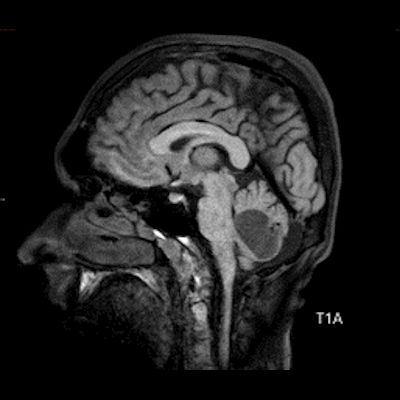

- B) Beyin MRG incelemesinde; 4. ventriküle bası etkisi oluşturan yaklaşık 3.5 cm boyutta, T2A hiperintens T1A hipointens kistik komponent (oklar) ve posteriorunda T1 ve T2A serilerde parankim ile izointens, içerisinde flow void alanların (oklar) izlendiği, post kontrast görüntülerde yoğun kontrast tutulumu gösteren mural nodül (oklar) barındıran düzgün sınırlı lezyon izlenmektedir.

- Kistik komponent: T1A hipointens, T2A hiperintens

- Mural nodül: T1A izo-hipointens, T2A orta derecede hiperintens olabilir.

- Kontrastlı incelemelerde mural nodül belirgin ve yoğun kontrast tutulumu gösterir. Ancak kist duvarında genellikle kontrastlanma beklenmez.

- T1 ve T2A görüntülerde flow voidler sıktır.